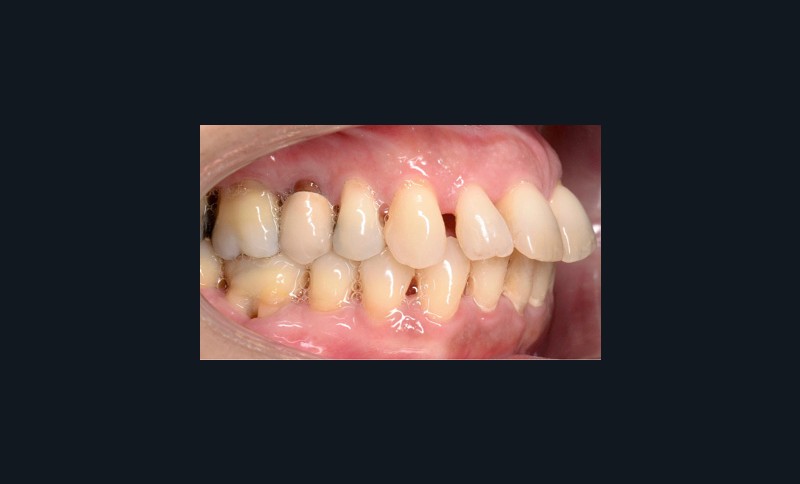

À l’examen endo-buccal (fig. 2), on note une formule dentaire complète (absence des 8) avec présence de restaurations multiples étanches, un bon contrôle de plaque et une parodontite de stade 4 grade C stabilisée [3], des récessions gingivales et des mobilités dentaires généralisées (degré 2, classification de Miller). L’arcade mandibulaire présente une courbe de spee importante avec égression du bloc incisivo-canin. Les milieux inter-incisifs sont alignés, le recouvrement est normal, le surplomb est augmenté à 3 mm et associé à des diastèmes et de la vestibulo-version des incisives maxillaires. Les relations antéro-postérieures canine et molaire sont en Classe I d’Angle.